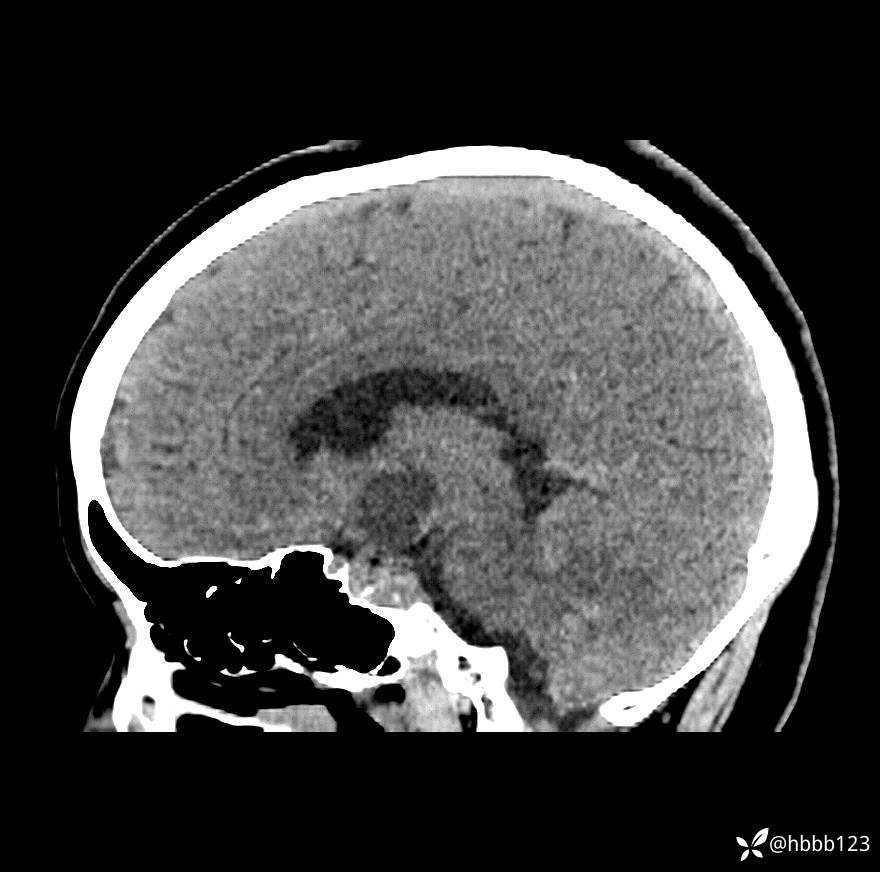

颅脑CT平扫:

矢状位重建: